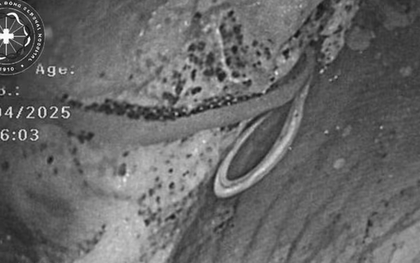

Một con giun dài gần 4cm đã trú ngụ trong amidan của cô gái trẻ sau bữa sashimi nhớ đời. Các bác sĩ đã phải dùng nhíp để gắp con giun này ra trước khi mọi chuyện trở nên tồi tệ hơn.